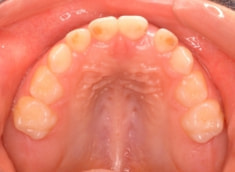

治療後(1年5ヶ月後)